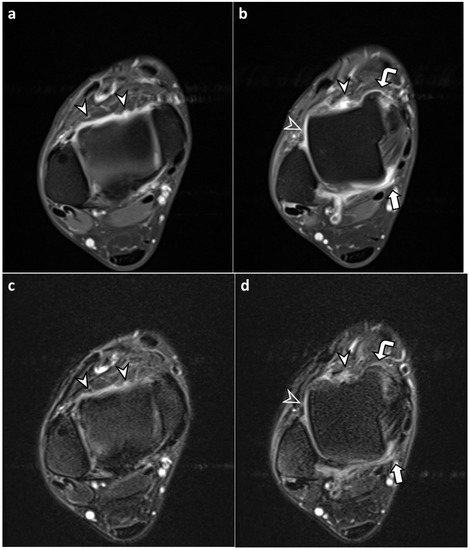

3.2. Synovial Visibility on FLAIR-FS and CE-T1 Images